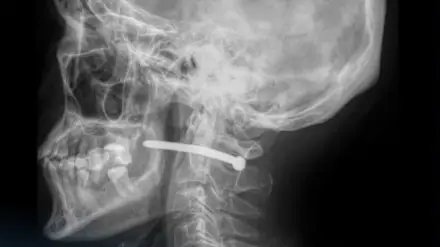

Казахстанец выстрелил себе в шею гвоздём Фото: пресс-служба многопрофильной городской больницы

"Как выяснилось, во время ремонтных работ он по неосторожности получил травму гвоздём из пневматического пистолета. Рентген показал, что гвоздь прошёл рядом с шейным отделом позвоночника", - сообщили подробности в пресс-службе медучреждения.

Врачи подчеркивают, что мужчине очень повезло: жизненно важные структуры не были задеты.

Челюстно-лицевые хирурги больницы удалили инородное тело, провели ревизию и обработку раны, а также наложили швы и стерильную повязку.